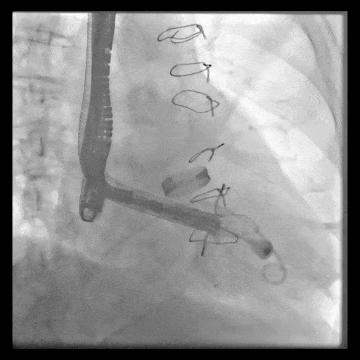

術中DSA顯示起搏器導線的干擾,右心室造影確定瓣環位置,操作空間小

術后DSA、超聲顯示人工瓣膜穩定性良好,瓣葉啟閉正常,無瓣周漏

術后DSA